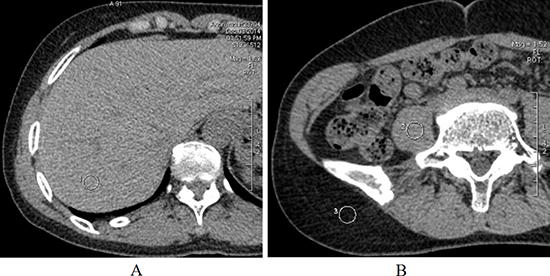

All images were randomized review by two experienced radiologists (with 8 and 6 years of experience in diagnosis of abdominal CT, respectively) independently. The standard deviation of the mean CT number was measured as the objective image noise, which was measured by placing a circular region of insterest of 80–100 mm2 in the paoas muscle, the right lobe of the liver, and the subcutaneous fat (Figure 4). Subjective image assessment included image quality, image noise, and diagnostic confidence. A score was derived for axial and coronal images with a soft-tissue window setting (width, 400 HU; level, 50 HU) on PACS system. The image quality was rated on a 5-point scale, (score1, poor image quality—not diagnostically acceptable for interpretation; score2, suboptimal image quality—worse-than-acceptable quality; score3, acceptable image quality—diagnostic interpretation possible; score 4, good image quality; and score 5, excellent image quality). A CT image that had an image-quality score of 3 or higher was considered acceptable for rendering an interpretation [25]. A subjective assessment of image noise and diagnostic confidence were rated on a 3-point scale (score 1, minimal; score 2, acceptable; and score 3, excessive—rendering diagnostic interpretation impossible) [25]. The readers also recorded the stone characteristics (number, location, size, and the distance from stone to skin [SSD]). The ureter was divided into three segment: the upper one-third of the ureter was from the renal pelvis to the superior border of the iliac crest; the middle one-third of the ureter was from the superior border of the iliac crest to the bottom of the sacroiliac joint; and the lower one-third of the ureter was from the bottom of the sacroiliac joint to the ureterovesical joint [27]. The radiation doses (mGy) were from the estimation of DLP that was generated by the CT scanner. The ED was calculated from the DLP by multiplying it by the conversion coefficient (0.015 mSv/mGy/cm).

Figure 4: ROI 1 (A) in the right lobe of the liver, ROI 2 and 3 (B) in the paoas muscle, and the subcutaneous fat. Abbreviations: ROI, region of interest.